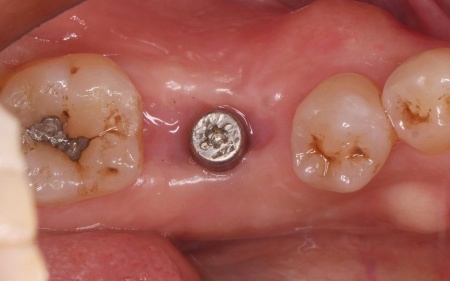

治療中

| 行ったご提案・治療内容 | 患者様はあごの骨に人工歯根を埋め、その上に人工歯を装着するインプラント治療を希望されています。 インプラント治療は自分の歯のような自然な見た目と噛み心地が期待できる一方で、自費診療のため費用が高くなることや外科処置を伴うため身体的負担がかかること、治療期間が比較的長くなる点がデメリットです。 また、安定したインプラント治療を行うためにはインプラントを支えられるあごの骨が残っているか、インプラントの上に人工歯を取り付けた際に噛み合わせの歯が邪魔をしないかなどを確認する必要があります。 その結果、十分な骨の量があり、噛み合わせの歯もインプラントを入れた際に自然に噛める位置に生えていたため、インプラント治療を行う条件は問題ないと判断しました。 【治療手順】 最後に見た目や噛み合わせに問題がないことを確認し、治療を終了しました。 |